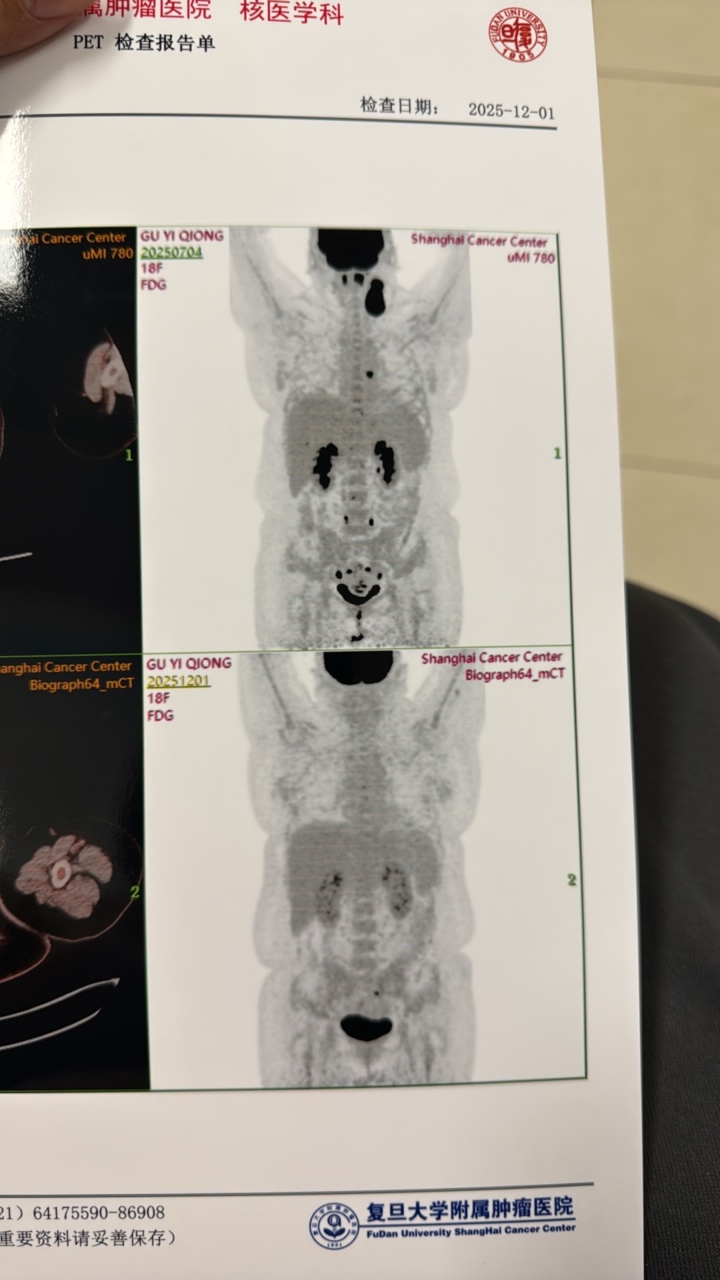

这个应该是PR吧……

但是我看我报告,黑色都没有了哇……结论也还好……看着,手臂那个刚刚跟医生讨论过了,可能是升白针导致的红肿,附件医生也说没啥问题,是生理性,医生前面看报告说3.6的那个,也有可能炎性导致……